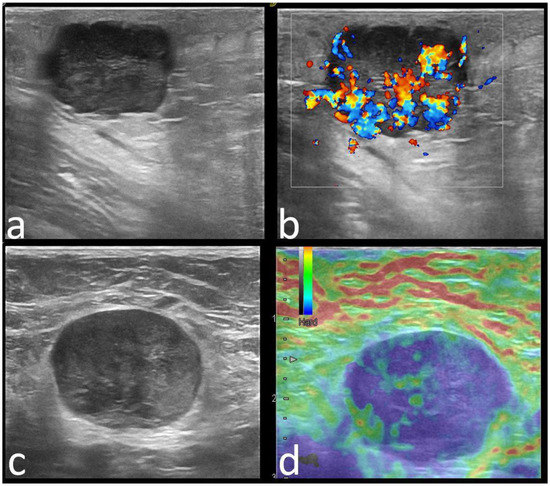

| Margins | |||

| Circumscribed | 22 (22.4) | 44 (30.3) | 0.226 |

| Echo pattern | 0.000 | ||

| Hypoechoic | 57 (58.2) | 100 (70) | |

| Heterogeneous | 36 (36.7) | 19 (13) | |

| Isoechoic | 5 (5.1) | 26 (17) | |

| Posterior features | 0.000 | ||

| None | 39 (39.8) | 71 (49) | |

| Enhancement | 27 (27.6) | 12 (8.3) | |

| Shadowing | 15 (15.3) | 54 (37.2) | |

| Combined | 17 (17.3) | 8 (5.5) | |

| Calcifications | 0.001 | ||

| Absent | 63 (64.3) | 122 (84.1) | |

| Present * | 35 (35.7) | 23 (15.9) | |

| Strain Elastography | 0.029 | ||

| Soft | 40 (40), 9 BGR | 30 (20.6), 1 BGR | |

| Hard | 58 (60) | 115 (79.3) | |

| US features (+/No. of patients) Orientation | NP (17/29) | NP (9/15) | NP (10/15) | P (7/15) | P (4/7) | P (4/6) | P (2/3) | P (2/3) |

| Margins | C (20/29) | NC (11/15) | NC (11/15) | NC (11/15) | C (5/7) | NC (5/6) | C (3/3) | NC (3/3) |

| Echo pattern | Hypoechoic (19/29) | Hypoechoic (9/15) | Heterogeneous (5/15) | Hypoechoic (11/15) | Hypoechoic (4/7) | Heterogenous (3/3) | - | Hypoechoic (2/3) |

| Posterior features | Enhancement (16/29) | Absent (9/15) | Shadowing (6/15) | Enhancement (6/15)/Combined pattern (5/15) | No posterior (4/7) | - | Enhancement (2/3) | - |

| Associated features | Hyperechoic rim (6/29) Soft elastography (11/29) | Calcifications (7/15) Hard elastography (12/15) | Calcifications (7/15) | - | - | Calcifications (3/6) Hyperechoic rim (3/6) | - | Calcifications (2/3) Architectural distortion (2/3) |